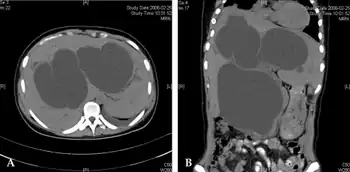

a)Congenital choledochal cyst (and intrahepatic bile duct dilation) b) choledochal cyst (with intrahepatic bile duct dilation.)